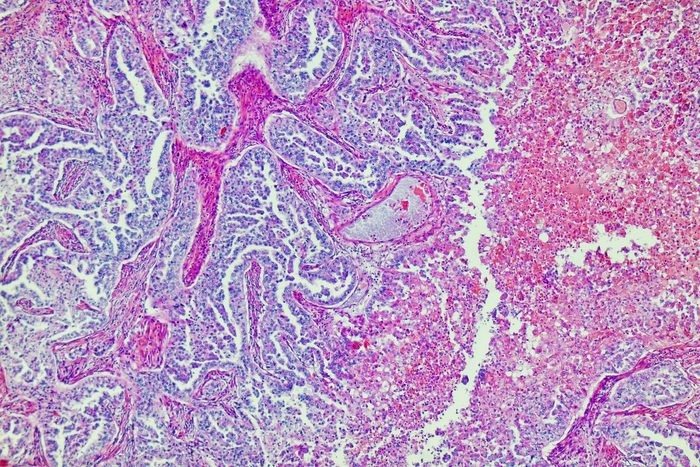

“The types of injury alcohol can cause range from fat accumulation in the liver, or steatosis, to inflammation of the liver, hepatitis, to scarring, or cirrhosis,” explains Dr. Lamia Haque, MD, MPH, an addiction specialist at Yale New Haven Hospital. Dr. Haque is a hepatologist (liver specialist) and addiction medicine physician who treats patients with liver diseases and co-occurring substance use disorders.

“This organ has a remarkable capacity for regeneration,” Dr. Ulm says. “With alcoholic liver disease, the proximate cause for many of the liver’s travails is an inflammatory response as the organ suffers its first hits from alcohol-related toxins, a process that feeds upon and exacerbates itself. Drinking cessation breaks this cycle of chronic inflammation that can eventually give rise to cirrhosis, a key first step in healing.”

“Fatty liver disease is one of the first hallmarks of hepatic (liver-related) injury and can occur acutely after a single binge-drinking session,” Dr. Ulm says. “It’s unsurprisingly quite prominent in a liver with more chronic insults to its function and well-being. When drinking is discontinued, the fatty ‘gunk’ throughout the tissue begins to dwindle.”